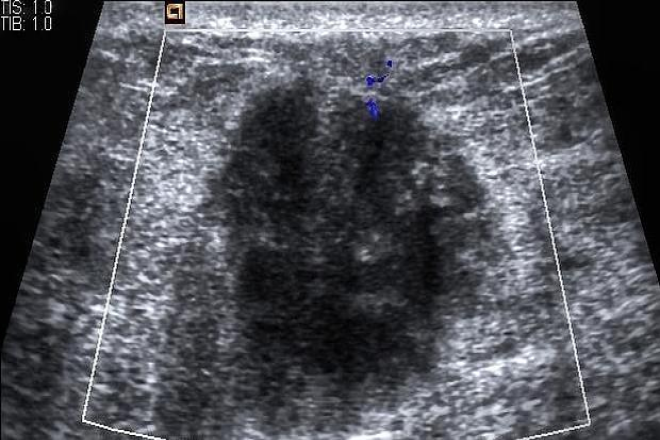

El ultrasonido principalmente puede visualizar las características macroscópicas de una masa y detectar diferencias en su apariencia global. Sin embargo, se ha demostrado que incluso las presentaciones submicroscópicas de un tumor pueden modificar su apariencia en el ultrasonido. El patrón de eco más frecuentemente observado en el cáncer de mama es un tumor hipoecoico (86%), y la sonomorfología está principalmente determinada por el tipo de tumor, no por la edad del paciente.

Una evaluación precisa de las masas en las mamas antes de proceder con más pasos diagnósticos o terapéuticos tiene un impacto crucial en la calidad del tratamiento y en el resultado para el paciente. La evaluación de la lesión por ultrasonido se basa en el sistema de clasificación ACR BI-RADS®- US, que proporciona una guía sustancial para predecir los aspectos malignos o benignos de un tumor. Es importante tener en cuenta que no todos los cánceres siguen las reglas de criterios típicos de ultrasonido para la malignidad, ya que pueden ocurrir variaciones según factores individuales como las características del paciente y la biología del tumor.